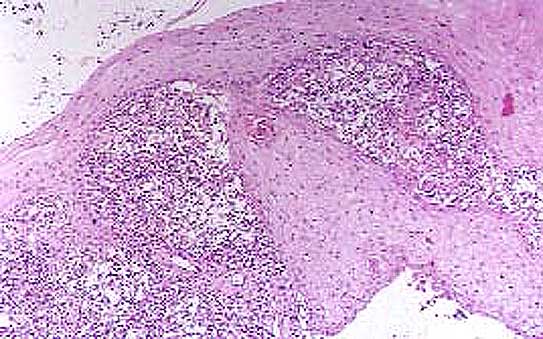

Fig. 21. Hiperplasia seudoepiteliomatosa en la Cromoblastomicosis, con microabscesos intraepidérmicos (H.E., Neg. X 40)

22.JPG (51846 bytes)